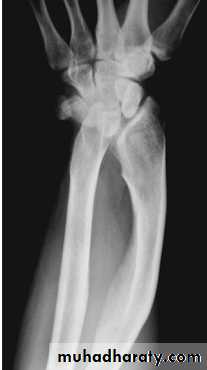

Radiological evaluation

Upper limbs

Lateral radiograph